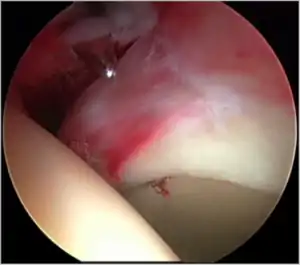

The acetabular labrum is a fibrous structure, which surrounds the femoral head. It forms a seal to the hip joint,[15] although its true function is poorly understood. Recent evidence has demonstrated that this hydraulic seal is vital for maintaining stability of the ball and socket joint [16] and reducing contact pressures of the femur to the acetabulum.[17] The labrum has also been shown to have a nerve supply and as such may cause pain if damaged.[18] The underside of the labrum is continuous with the acetabular articular cartilage so any compressive forces that affect the labrum may also cause articular cartilage damage, particularly at the junction between the two, the chondrolabral junction. The labrum may be damaged or torn as part of an underlying process, such as FAI or dysplasia (shallow hip socket), or may be injured directly by a traumatic event. Depending on the type of tear, the labrum may be either trimmed (debrided) or repaired. Removing or debriding the labrum is becoming less popular as the latest research shows that results are more predictable in the long term if the labrum can be repaired. Various techniques are available for labral repair, mainly using anchors, which may be used to re-stabilise the labrum against the underlying bone, allowing it to heal in position.

New techniques are prevalent in hip arthroscopy. There is good evidence to support the creation of a new labrum by performing a labral reconstruction if the patient has previously had a labral debridement, has an ossified labrum, or the current labrum is too small or injured for a repair.[16] Labral reconstruction involves creating a new labrum either from the patients own tissue (autograft) or from cadaver tissue (allograft). The new labrum is then anchored into position with bone anchors and the hip then goes through extensive rehab.